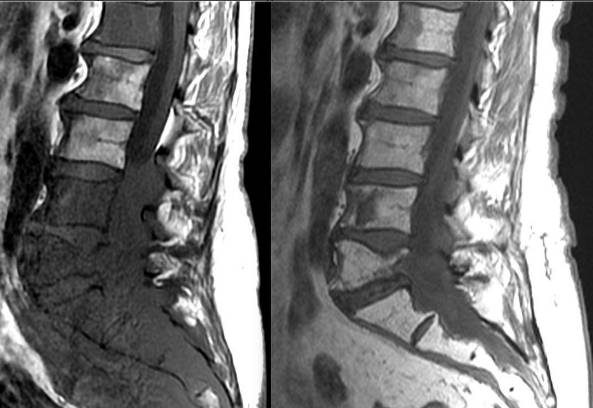

Остеохондроз

Если у человека в шейном отделе на позвоночнике появилась шишка, что-то напоминающее горбик, то есть вероятность того, что это шейный остеохондроз.

Причиной может стать:

- травматизм позвоночного столба в определенной зоне;

- наличие сколиоза или другого искривления;

- сидячая работа (программисты, учителя, бухгалтера и пр.);

- малоподвижный образ жизни.

К симптоматике шейного остеохондроза относят:

- болезненность в грудине, плечевом поясе;

- головные боли и головокружение;

- потерю чувствительности верхних конечностей;

- хруст при повороте шеи.

Все вышеперечисленные симптомы притупляются в состоянии покоя. Во время двигательной активности и при выполнении какой-либо работы дискомфорт усиливается.